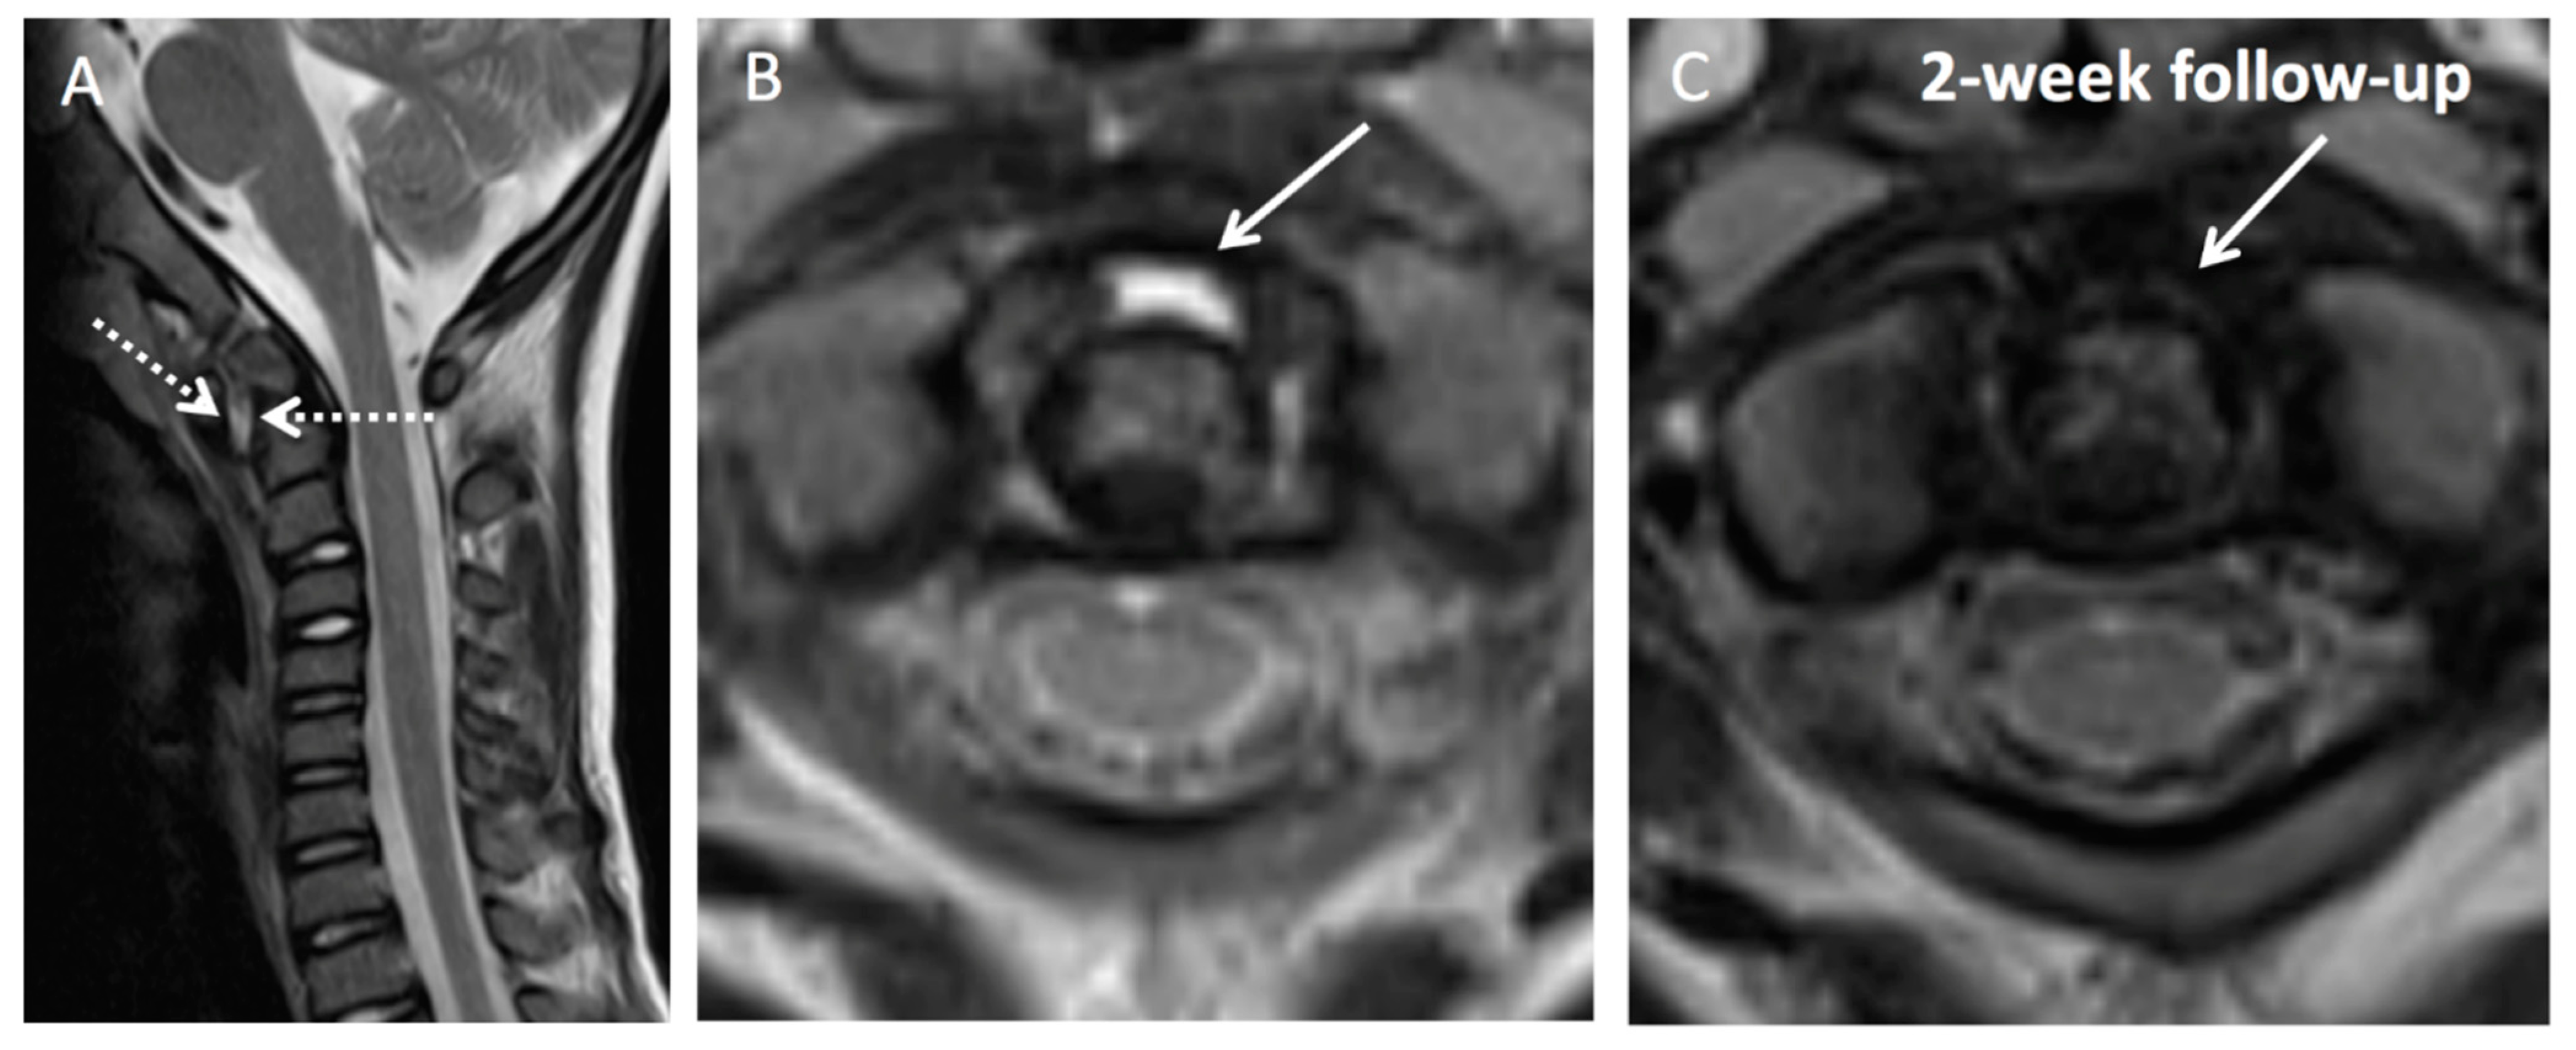

Illustration of Three Pediatric Cases of MRI in Inflammatory Nontraumatic Atlantoaxial Rotatory Subluxation